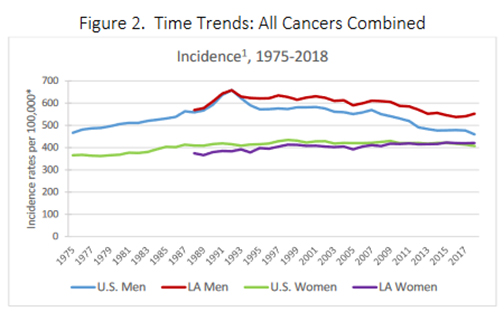

LSU Health New Orleans Releases Latest Report on Cancer in Louisiana

The Louisiana Tumor Registry at LSU Health New Orleans School of Public Health has published Cancer in Louisiana Volume 38. It includes information on cancer incidence and deaths between 2016 and 2020, incidence and mortality trends from 1988 to 2020, survival statistics for cases diagnosed from 2009 to 2019, and followed into 2020, and prevalence of cancer cases diagnosed from January 1, 2000, to January 1, 2020. More

LSU Health’s LA Tumor Registry Publishes Latest Statewide Cancer Incidence, Mortality & Survival Info

LSU Health New Orleans’ Louisiana Tumor Registry has published the latest volume in its annual Cancer in Louisiana monograph series. Cancer in Louisiana, Volume 37, 2015 – 2019, documents cancer incidence and mortality from 2015 to 2019 in Louisiana, as well as incidence and mortality trends from 1988 to 2019. It also includes survival statistics for cases diagnosed from 2008 to 2018 and followed into 2019, as well as prevalence for cancer cases diagnosed from January 1, 2000, to January 1, 2019. More

Latest Cancer in LA Volume Contains New Incidence & Mortality Tables for Industrial Corridor

LSU Health New Orleans School of Public Health’s Louisiana Tumor Registry has published the latest report on cancer incidence and mortality in Louisiana – Cancer in Louisiana 2014-2018 (Volume 36). More